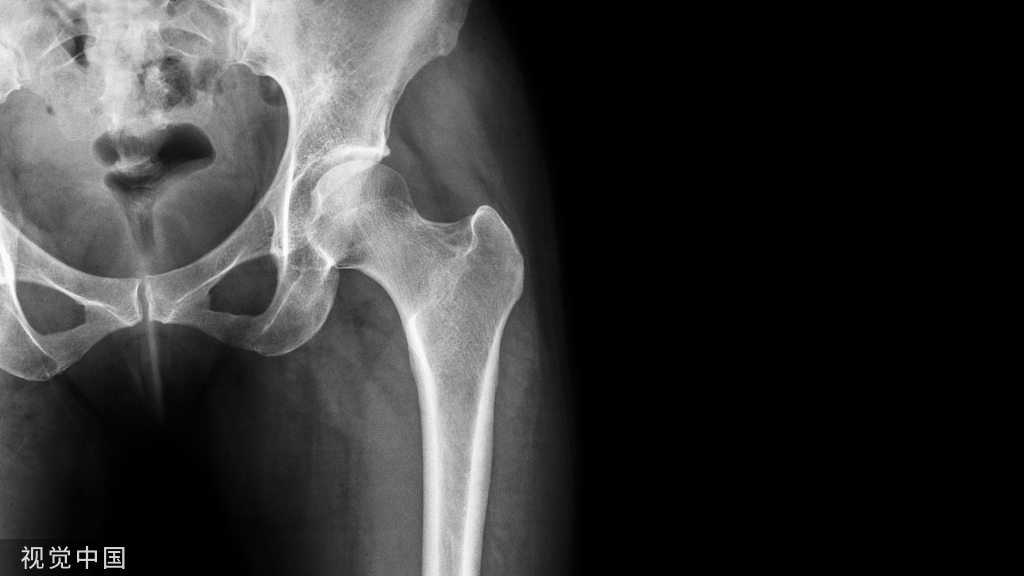

骨关节炎(OA)是常见的关节退行性疾病,以关节软骨磨损、溃疡、皲裂、脱失,关节软骨下骨及周围骨反应、关节周围肌肉萎缩、滑膜炎性反应,关节疼痛、活动受限、畸形与功能障碍为主要症状,易发生于中老年患者。研究显示,OA可显著升高下肢深静脉血栓栓塞、心血管事件、髋部骨折及全因死亡率的风险,其病因与年龄、炎症、肥胖、创伤及遗传等有关。